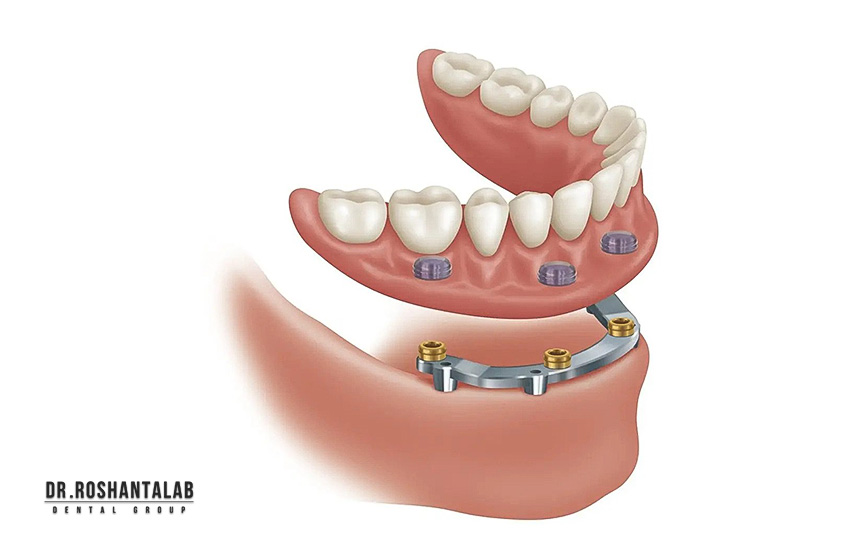

اوردنچر

با همه مزایایی که پروتز کامل دارد اما معایبی نیز دارد. از جمله اینکه دارای استحکام کافی نیست و روی لثهها میلغزد. بدین جهت از اوردنچرها که نوعی پروتز ثابت است و در واقع ترکیبی از دندان مصنوعی و ایمپلنت هستند، استفاده میشود. از این رو استحکام بیشتری دارند و بهتر درون دهان گیر میکنند. تعداد ایمپلنت های اوردنچر با توجه به شرایط استخوان، لثه و سایر فاکتورها، مشخص میشود.

انواع اوردنچر چیست؟ هر کدام از انواع اوردنچر چه ویژگی هایی دارند؟ کدام یک از انواع اوردنچر بهتر است؟